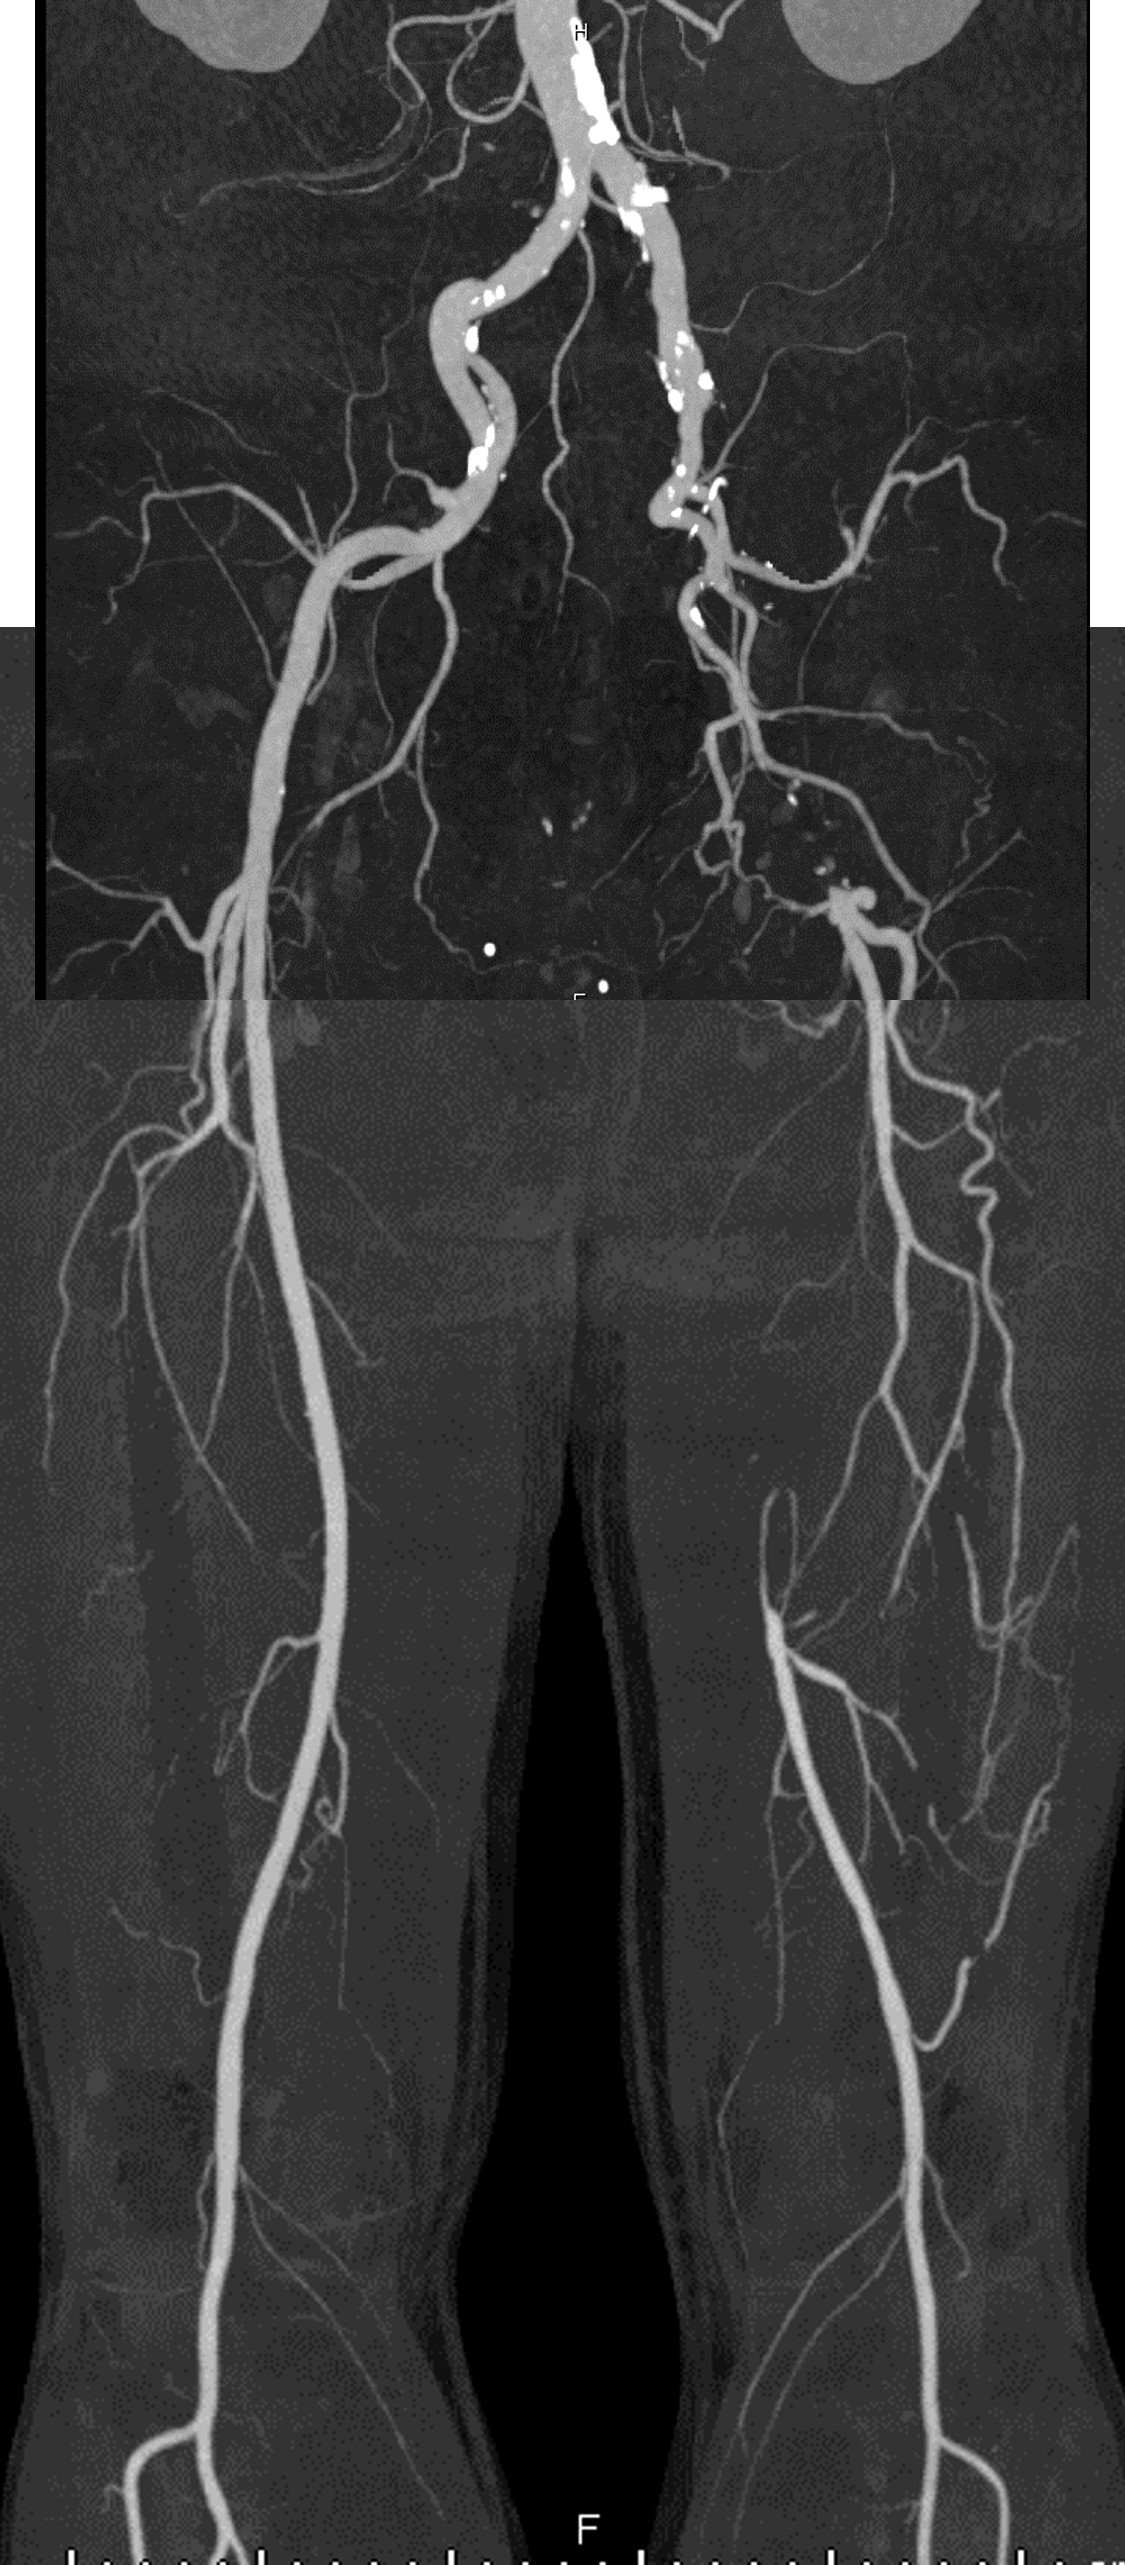

CT angiography showed total occlusion of the left external iliac artery (EIA) with preserved flow to the distal superficial femoral artery (SFA) via collaterals. Electrocardiography revealed a normal sinus rhythm without arrhythmia. Echocardiography was normal, and laboratory data showed no evidence of hypercoagulable disorder.

First EVT: Via right femoralcrossover approach, total EIA occlusion was confirmed by angiography. Thrombusaspiration with a TVAC catheter (Nipro, Osaka, Japan) restored partial flow, and two bare-metalstents (BMS, Smart, Cordis, Miami Lakes, FL) were implanted in the EIA.Intravascular ultrasound (IVUS) demonstrated that the EIA lesion was thromboticrather than atherosclerotic. In addition, residual thrombus was detected in theproximal SFA, and POBA was performed for this segment. Second EVT (2 weeks later from the first EVT): Re-occlusionof the EIA stent was observed. Indigo aspiration retrieved large amounts of redthrombi. Residual thrombus remained at both stent edges; two additional BMSswere placed proximally and distally. SFA thrombus attachment was noted, andtriple therapy (a low-dose direct oral anticoagulant plus dual antiplatelettherapy) was initiated. Third EVT (4 weeks later from the first EVT): Recurrentin-stent occlusion occurred. After thrombus aspiration with TVAC, persistentSFA stenosis was identified as a thrombogenic source. A stent graft (Viabahn,W. L. Gore & Associates, Flagstaff, AZ) was implanted in the SFA, and oneadditional Smart stent was deployed overlapping the distal edge of the Viabahnand the previous EIA stents. Final angiography showed excellent flow with noresidual thrombus. The patient remained symptom-free with confirmed stentpatency at follow-up.